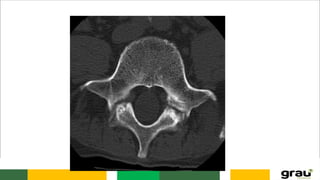

VÉRTEBRAS

CORPO

CANAL MEDULAR (FORAME

VERTEBRAL)

FACETA ARTICULAR

PROCESSOS TRANSVERSOS

PROCESSO ESPINHOSO

VÉRTEBRAS CORPO CANAL MEDULAR (FORAME VERTEBRAL) FACETAARTICULAR PROCESSOS TRANSVERSOS PROCESSO ESPINHOSO